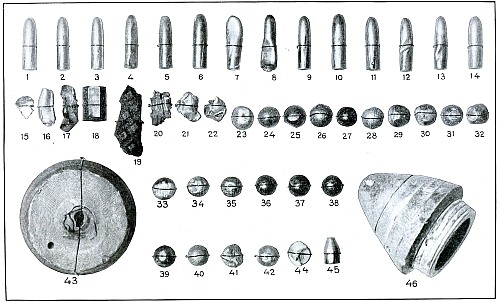

Projectiles.—The projectiles which figure in the illustrations

were those employed by the nations at war. They are derived (1) from

the Turkish pointed bullet weighing approximately 15.0 grams—it is

fired from the German Mauser and has all the ballistic values of the

projectile from this weapon; (2) the Bulgarian bullet, blunt nosed

or ogival headed and the same as the steel-jacketed bullet of the

Austrian Mannlicher; (3) shrapnel balls and fragments of the shrapnel,

and (4) fragments of steel shells from field artillery.